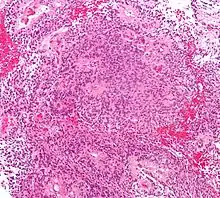

Astrocytome

Divers systèmes de catégories ont été proposés dans la littérature au fil du temps pour classer la malignité des astrocytomes. Depuis 1993, le système d'évaluation à quatre niveaux proposé par l' Organisation mondiale de la santé (OMS) est le plus largement utilisé et appliqué. Elle est basée sur quatre caractéristiques histologiques : augmentation de la densité cellulaire, mitose, prolifération endothéliale et nécrose. Par la suite, les astrocytomes de grade I, tels que les astrocytomes pilocytiques, sont généralement d'histologie bénigne. Astrocytomes II. Les grades (diffus) montrent une densité cellulaire accrue comme seule caractéristique histologique et sont des néoplasmes avec un degré d'infiltration inférieur. Les astrocytomes III montrent une mitose importante. grade (anaplasique). Et la prolifération ou la nécrose endothéliale sont observées dans les astrocytomes IV. degrés, les soi-disant glioblastomes.

Astrocytomes anaplasiques

L'astrocytome anaplasique est une tumeur cérébrale maligne caractérisée par une croissance diffuse, une densité cellulaire accrue et des figures de division nucléaire. Elle est issue d'une population cellulaire spécifique du système nerveux central, les astrocytes. Selon la classification OMS des tumeurs du système nerveux central, la tumeur correspond à une tumeur de grade III.

Glioblastome

Les tumeurs des cellules gliales les plus courantes et les plus malignes sont les glioblastomes. Ils consistent en une masse hétérogène de cellules d'astrocytome peu différenciées principalement chez l'adulte. Ils surviennent généralement dans les hémisphères cérébraux, plus rarement dans le tronc cérébral ou la moelle épinière. Sauf dans de très rares cas, comme toutes les tumeurs cérébrales, elles ne s'étendent pas au-delà des structures du système nerveux central.

Les oligodendrogliomes sont relativement rares, représentant moins d'environ 5 % de toutes les tumeurs cérébrales primaires et pas plus d'environ 10 à 15 % de tous les gliomes. Ces tumeurs sont divisées en lésions de bas grade et anaplasiques. L'oligodendrogliome anaplasique est caractérisé par une augmentation de la densité cellulaire, de la mitose, de la prolifération endothéliale et du polymorphisme nucléaire, et de la nécrose.